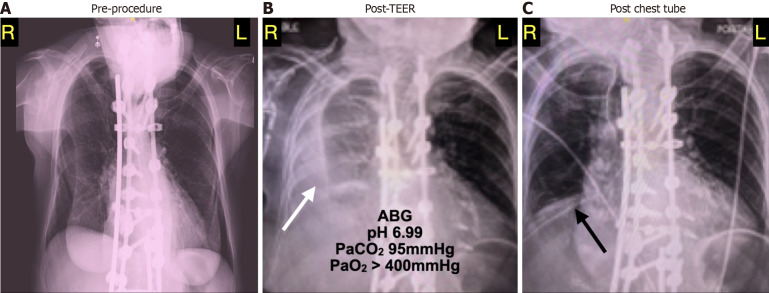

Case summary: A 74 year-old woman with severe MR, a left ventricular ejection fraction of 45%, and a small circumferential pericardial effusion underwent TEER of the mitral valve. After the placement of two MitraClips, the MR was assessed as mild to moderate. Within 10-20 minutes after the completion of the case, the patient was dyspneic and hypotensive despite volume resuscitation. Point-of-care ultrasound (POCUS) showed no changes in cardiac contractility, valve function, or the pericardial space. The right heart chambers appeared small with right atrial (RA) diastolic collapse. There was no evidence of venous congestion. Further exam showed a large right pleural fluid collection. Given the clinical scenario of dyspnea, hypotension, and diastolic RA collapse, low-pressure tamponade was suspected. A thoracentesis expelled 1200 mL of blood with immediate hemodynamic improvement. The patient made an uneventful recovery.

Conclusion: The application of POCUS is crucial for detecting, diagnosing, and properly managing cardiac dysfunction and procedural complications associated with TEER. While tamponade is classically associated with a pericardial effusion and vena caval plethora, their absence does not dismiss the suspicion or diagnosis of tamponade. This case highlights the value of POCUS in assessing low-pressure tamponade caused by a large, pressurized pleural effusion. Clinical suspicion, supported by POCUS findings, was confirmed by a thoracentesis that resulted in immediate hemodynamic improvement.